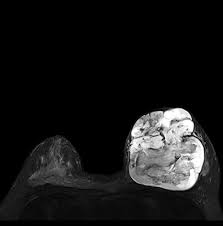

List of Qualimed Hospital Branches. Price Inquiry Contact Number. Magnetic Resonance Imaging MRI is a diagnostic imaging technology used to create images of internal organs and structures of the body using radio waves and powerful magnets.